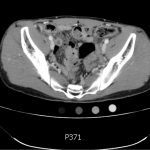

The CT abdomen/pelvis with intravenous contrast shows a dilated appendix (see red outline) with thickened, hyperenhancing wall (see blue outline) best visualized in the axial and coronal planes.